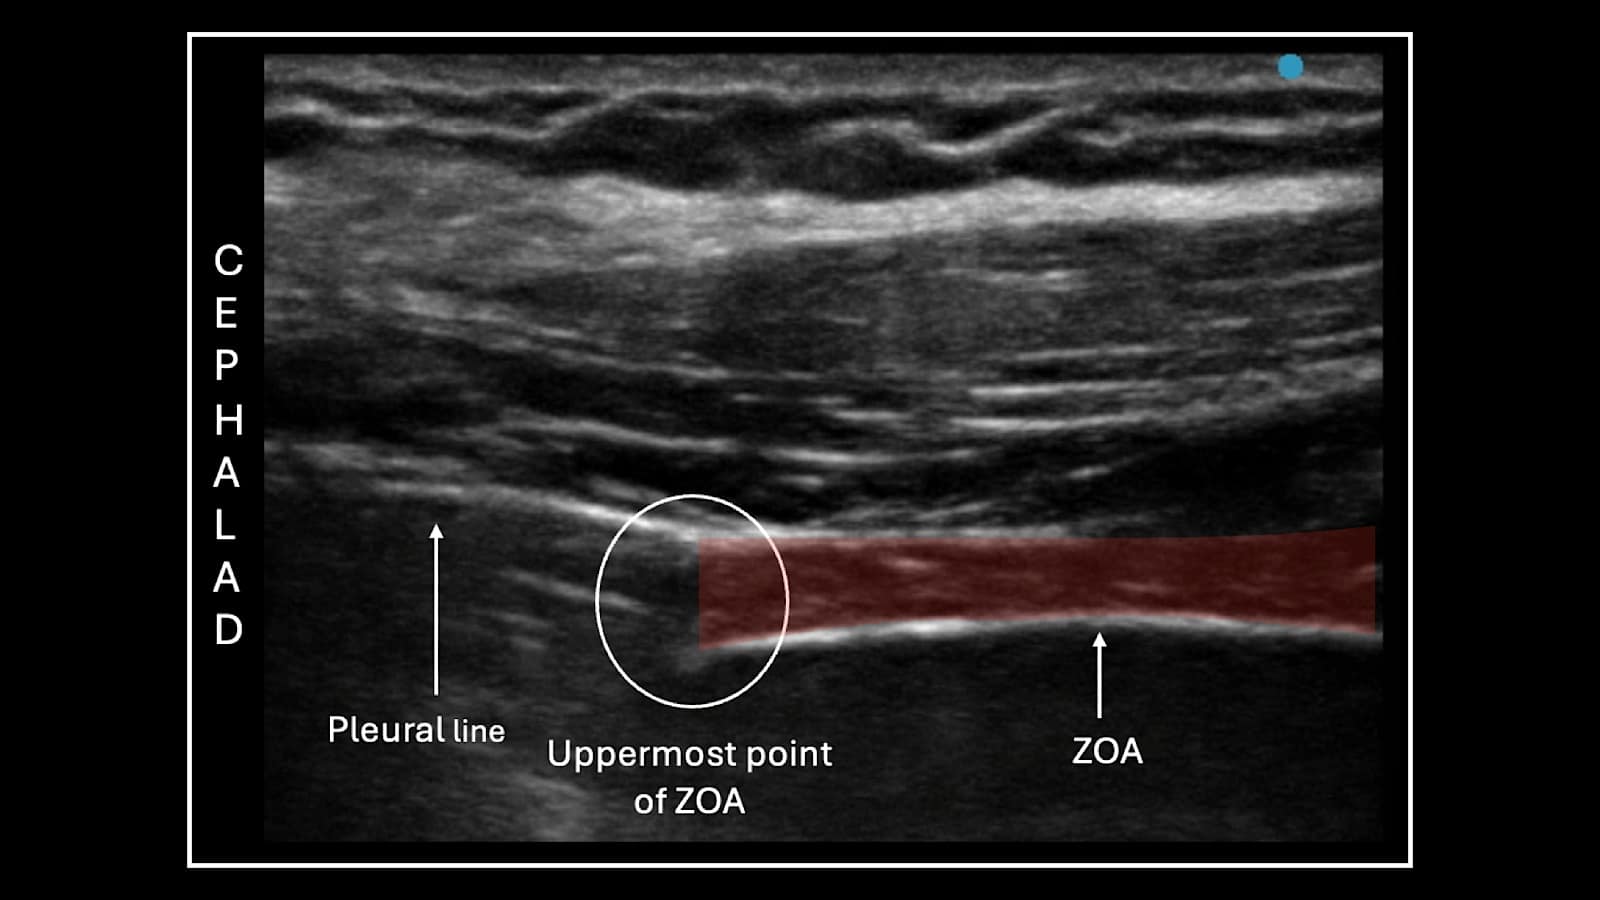

The ZOA is the area in the lower portion of the thorax where there is no lung tissue between the parietal pleura of the chest and the diaphragm is in direct apposition with the thoracic wall (Figure 5). This allows for an acoustic window with a direct view of the lateral aspect of the diaphragm. The diaphragm lies deep to the chest wall and has a characteristic three-layer pattern on ultrasound. There is a central muscular layer that is hypoechoic with a hyperechoic reticular pattern, and it is sandwiched between two hyperechoic layers, which represent the peritoneum and the parietal pleura. The area where both the lung sliding and the diaphragm can be viewed in a single image is the cephalad border or uppermost point of the ZOA (Figure 6). This allows for visualization of the cephalad aerated lung (with lung sliding), which obscures the visualization of the diaphragm and the ZOA caudal to the lung sliding where the diaphragm will be visible (transition point). This is the area where the measurements are taken.

Reproduced with permission from Giron Arango Medicine Professional Corporation.

This method utilizes the same ZOA for evaluation that is assessed during the zone of apposition muscle thickening approach. But in this case, instead of evaluating the diaphragm muscle, the location of the uppermost point of the ZOA (transition point) is interrogated (where the aerated lung meets the ZOA). During normal inhalation, the transition point is displaced caudally. A deep inhalation accentuates this caudal movement. The relative position of the transition point in relation to the chest surface is evaluated. The caudal aspect of the visceral pleural line can normally be seen descending by about two intercostal levels during deep inhalation. In the presence of diaphragmatic paresis, there is minimal to zero movement.

This method only allows for a qualitative assessment of the diaphragm; however, a semiquantitative analysis can be performed by marking the point at the uppermost point of the ZOA on the patient’s skin during both inspiration and expiration. Two markings can be labelled on the skin with a marker at the most cephalad and most caudal position at the end of deep inhalation and at end exhalation, respectively. A tape measure can be used to find the distance between the two lines. This technique has shown to be equally successful on both sides of the thorax.16,33